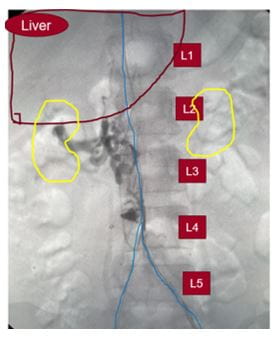

“The patient presented to us at UH with left leg phlegmasia due to IVC and bilateral iliofemoral DVT which was confirmed on duplex and CT scan,” Dr. Harth says.

Her overall clinical history, presentation and imaging was consistent with the patient having a congenital occlusion of the retro-hepatic inferior vena cava, the portion of the major vessel lying behind the liver.

To address the problem, Dr. Harth performed a staged complete IVC and bilateral iliofemoral thrombectomy and recanalization. In addition, she reconstructed the patient’s congenitally occluded retro-hepatic IVC with IVC stenting.

“Repeat mechanical thrombectomy with a larger device of the residual thrombus allowed us to remove more of the chronic, sub-acute thrombus that we couldn’t remove with suction thrombectomy,” Dr. Harth says. “We then proceeded to dilate up her retro-hepatic IVC which originally started off as an occluded vessel, to a 20 mm diameter with intravascular ultrasound and venographic guidance and ultimately deployed a 20 mm stent.”